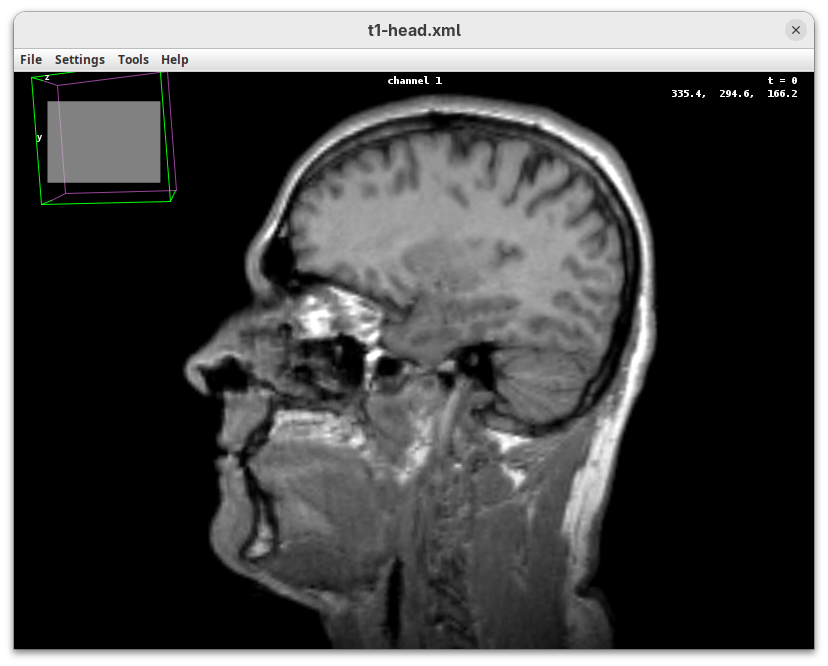

To get started, make sure the head dataset is still open.

- Go to

Plugins>3Dscript>Interactive Animation.

Two new windows will open: 3D Animation with the initial rendering of the data and Interactive Raycaster with all the fields to control the rendering parameters.

Contrast

The Contrast section shows a histogram of pixel intensities of the image for each channel, which we can choose using the dropdown menu. We can set the minimum, gamma, and maximum values for the intensity and alpha (transparency) properties of each pixel. The weight option controls the general opacity of the channel (0=invisible, 100=visible). There’s also more advanced options like lighting and rendering algorithm which we’ll simply use the default states as they are usually good for most use cases.

Adjusting the intensity and alpha values is the most impactful way to improve the 3D rendering. With the intensity setting we can define which pixel value in the image corresponds to total black (minimum) and which corresponds to total white. It’s the same as in the standard Brightness & Contrast tool. By default, 3Dscript will load these values from the original stack. In this case, it loaded min=3 and max=521.

Let’s change these values to see how it impacts the 3D rendering.

- Change the intensity minimum to

250.

You will see that the darkest parts of the rendering will become even darker and no longer visible. We are losing real information from the data; we do not want that.

- Set the

minto0, for now. - Then, change the

maxto250.

The brightest parts of the rendering will become all white. It is so bright that we can no longer resolve details of the surface. We are losing information and also do not want that.

maxto500.

Note that when you change an intensity value, the min/max black line in the histogram moves. You can also grab the line and move it manually to change the values.

The blue line represents the alpha values. In 3D rendering, a pixel has a transparency value linked to its intensity. The alpha min defines the value for full transparency and the max the value for full opacity.

- Set the alpha

minto250.

This will make darker pixels more transparent and information gets lost.

- Set it to

0.

By default 3Dscript sets the gamma value of alpha to 2.0. That’s a good default for fluorescence microscopy (see the next dataset below), but since this is MRI data, we need to tweak it a little differently.

- Set the alpha gamma value to

1.0.

Note that this improves the visualization as the head’s surface becomes better visible.

- Now set the alpha

The surface will become even more solid because we are defining that pixels that have a value above 250 will be fully opaque.

- To compare, set alpha

maxto5000.

You will notice that the sample will become more transparent. Even the brain inside the skull will be visible.

- Set alpha

maxback to500.

Generally, setting the intensity and alpha to the same values is a good starting point for optimizing the rendering.

Transformation

The transformation menu has controls for rotating, translating, and scaling the sample. We can either add values or manually interact with the 3D Animation window to reorient the sample. Let’s try the latter.

- Left-click on the head and move it around.

That’s a great way to see your sample from different angles. And note that the values in the Transformation panel get updated every time you move the sample interactively. In this way you can roughly position the sample and then check and update the precise values for the target transformation.

- Press

Resetand change theRotation Yto180to look at the right side of the head.

- Now change

Scaleto5andTranslation Xto-500to focus on the nose.

Resetto return the sample to its original position.